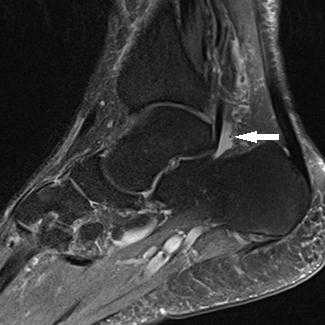

Прежде всего, это боль по задне-внутренней поверхности голеностопного сустава. Возможно «защёлкивание» большого пальца при его сгибании. Хруст, крепитация по задне-внутренней поверхности голеностопного сустава при активных движениях. При физикальном осмотре определяется боль при сгибании большого пальца через сопротивление, при форсированном подошвенном сгибании в голеностопном суставе, при этом боль отсутствует в области первого плюсне-фалангового сустава. Для диагностики повреждения сухожилия длинного сгибателя большого пальца стопы целесообразно выполнение МРТ, при этом обнаруживается скопление жидкости вокруг сухожилия на уровне голеностопного сустава, изменение сигнала от самого сухожилия.

Повреждения сухожилия сгибателя большого пальца стопы распространённый вид травмы в таких группах риска как танцоры (прежде всего балета), гимнасты и скалолазы. Эти группы людей объединяет существенная перегрузка сгибателя большого пальца стопы при выполнении толчков и зацепов, стояния на пуантах. Вторым названием данной патологии является «тендинит танцора». В остальной популяции данные повреждения встречаются крайне редко. Так как сухожилие длинного сгибателя большого пальца проходит в фиброзно-костном канале позади внутренней лодыжки и голеностопного сустава, оно оказывается как бы перекинутым через задний отросток таранной кости, как верёвка перекинутая через блок.

При его хронической травматизации дегенеративные изменения приводят к его утолщению и уплотнению, вызывают его сдавление и ущемление. Может возникнуть так называемый задний импиджмент голеностопного сустава. В случае если в толще сухожилия возникают узелки, может появиться такой симптом как «триггерный палец», когда большой палец согнувшись «защёлкивается», и разогнуть его можно только через боль и приложив значительное усилие. При длительно текущем процессе возможно рубцовое сращение сухожилия со своим каналом, что приводит к псевдо-ригидной деформации первого плюсне-фалангового сустава.